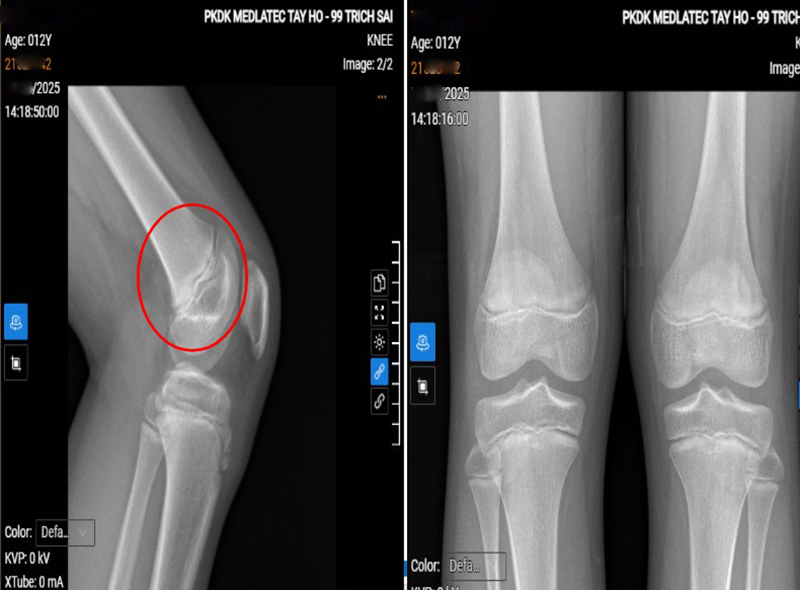

| Phim chụp tổn thương của bệnh nhi. |

Để xác định nguyên nhân, bác sỹ chỉ định siêu âm, X-quang và chụp MRI khớp gối. Kết quả siêu âm cho thấy phù nề nhẹ tại điểm bám gân bánh chè; X-quang ghi nhận hình ảnh theo dõi hoại tử vô khuẩn lồi củ xương chày; MRI phát hiện phù nhẹ dây chằng chéo trước, phù xương và mô mỡ quanh lồi củ chày, tất cả gợi ý bệnh cảnh viêm lồi củ trước xương chày.

Từ các kết quả này, trẻ được chẩn đoán viêm lồi củ trước xương chày trái và được kê đơn điều trị ngoại trú, kết hợp giảm vận động mạnh, chườm đá sau khi vận động, đeo băng thun bảo vệ gối cùng các biện pháp hỗ trợ để giúp hồi phục và hạn chế tái phát.